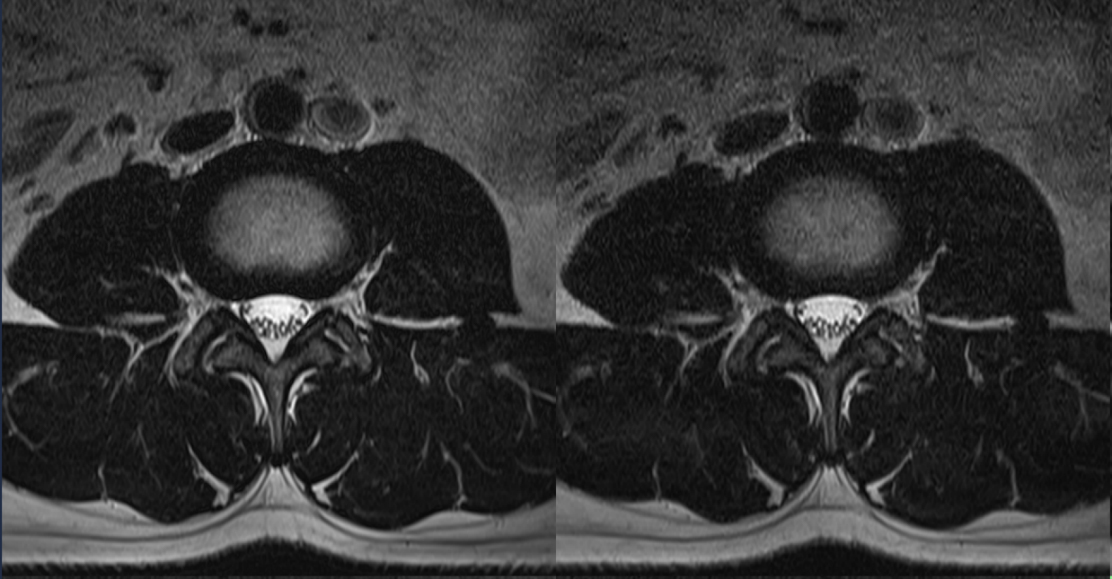

без Compressed Speeder

с помощью Compressed Speeder

Время сканирования 2:48

Время сканирования 1:24

Original

Compressed SPEEDER 2.0

Compressed SPEEDER 2.5

Время сканирования 3:10

Vantage Orian 1.5T

Время сканирования 1:46

Время сканирования 1:18